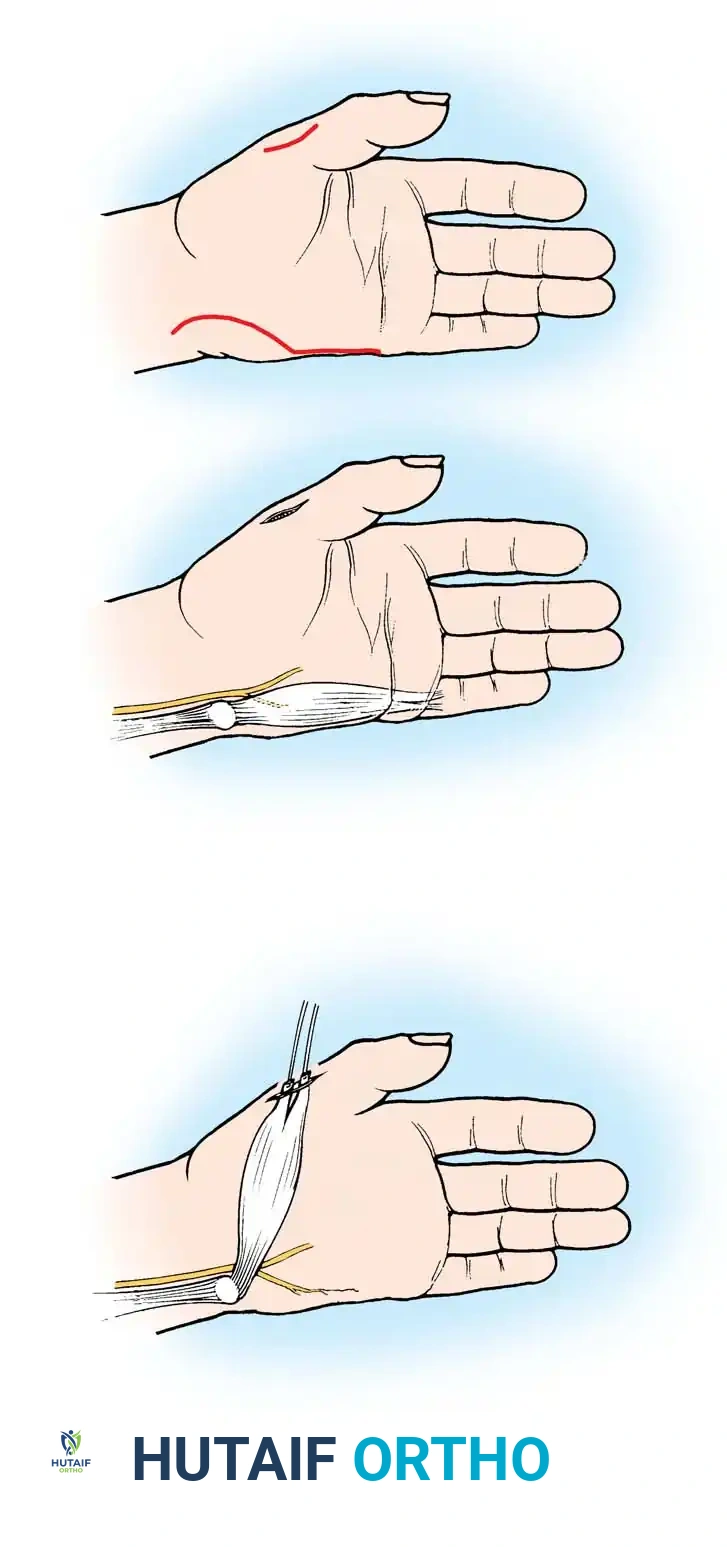

Surgical Interventions in Transverse Deficiencies

Surgical indications for transverse deficiencies are exceedingly rare. Epps, Burkhalter, and McCollough reported that out of 1,077 children